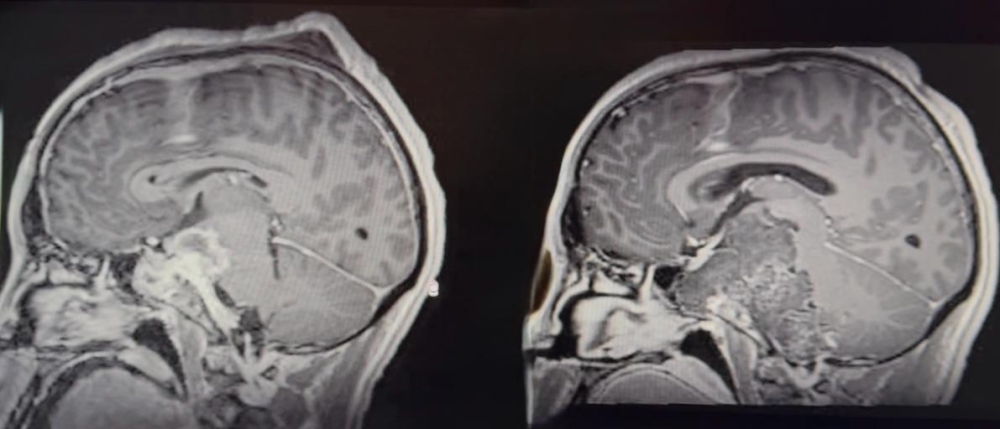

جدة.. استئصال ورم حبلي نادر من قاع جمجمة مريض خلال 35 ساعة

فريق سعودي متخصص في مستشفى الملك فهد في جدة – عضو تجمع الصحة الثاني لجدة – في القضاء على ورم حبل نادر ومعقم من الجزء السفلي من الجمجمة ، خلال ثلاث عمليات جراحية متتالية امتدت 35 ساعة ، والتي وضعت الفريق في نخبة المراكز القليلة على مستوى العالم التي تؤدي هذا النوع من العمليات الخطرة والمعقدة." الهدف ="_فارغ"> الفريق الجراحي." الهدف ="_فارغ"> المراكز الطبية المرجع في جميع أنحاء العالم. />

ضم الفريق مجموعة من الأطباء المقيمين الذين تم تدريبهم في الزمالة السعودية لجراحة الأعصاب ، من بينهم الدكتور عبد العزيز باسارا ، الدكتور ديما الأسهلي ، الدكتورة مريم أناني ، الدكتورة زياد العزانية ، إلى جانب فريق التخدير المتميز الذي يقوده الدكتور زاكاريا شاوكي والدكتور أحمد حليلي ، ومرضى تشرب. -متيري والممرضات الصغيرة توماس.